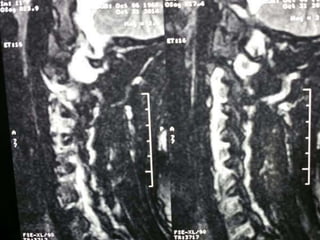

77 year old woman with h/o hand weakness/numbness/ataxia

Prior acdf 14 years ago

Cephalomedullary angle 135-175

c2c3

c3c4

c4

c4c5

c5c6

c6c7